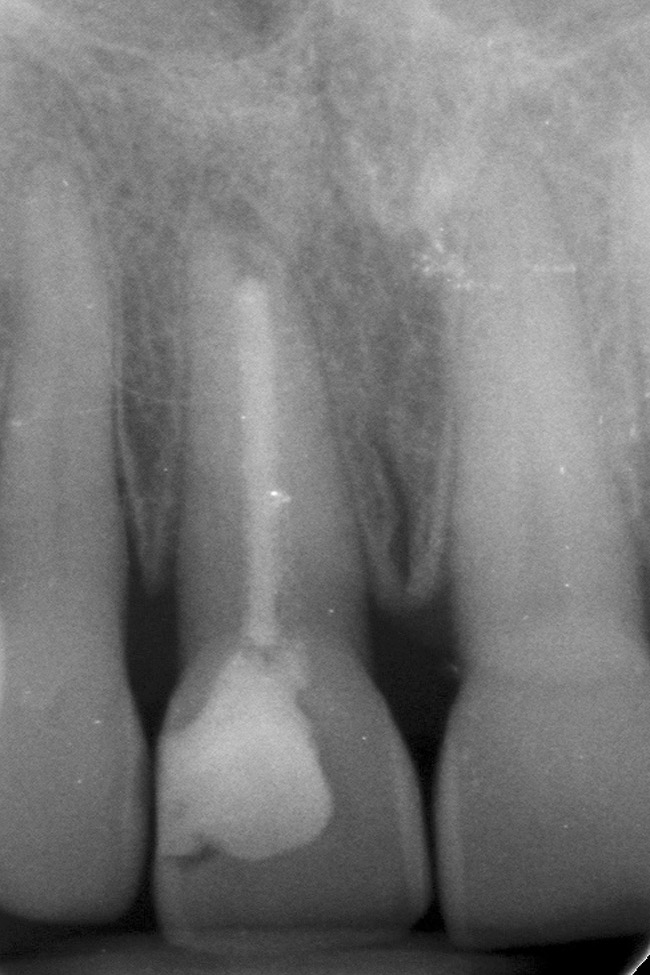

Figure 2  A radiograph finds no pulp chamber in the slightly dark central incisor and a silver point on the darkest lateral incisor. A titrated approach to bleaching was needed using individual tooth treatments.

Figure 2

Figure 3  A radiograph will indicate whether the dark color is related to materials remaining in the pulp chamber, leaking restorations, caries, internal resorption, or failed endodontic therapy.

Figure 3